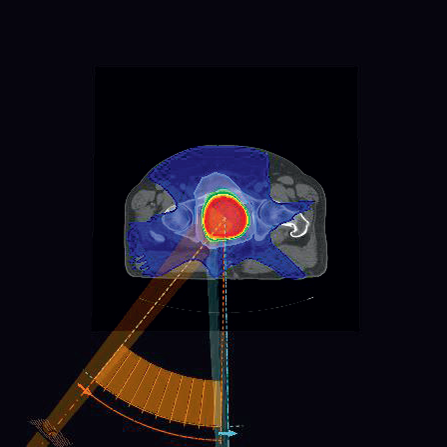

Figure 2

Figure 2: CDR plan for prostate patient P1. For the CDR plan, the MU per gantry angle is constnant. The total MU is 465 MU (5.19 MU/cp) and the delivery time is 93 seconds.